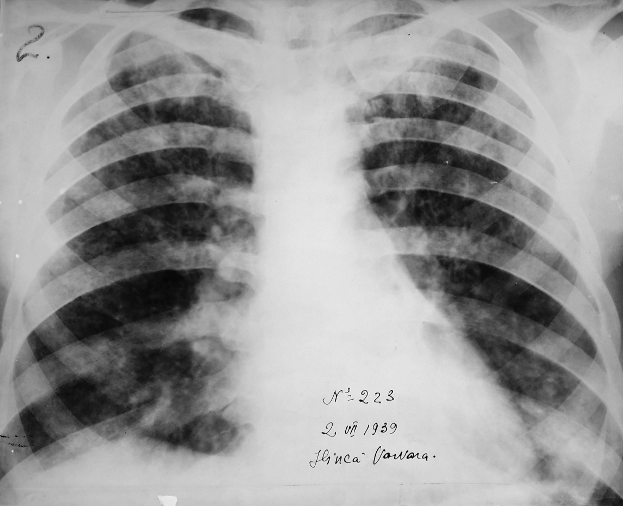

Rx toracică, incidență P-A

DESCRIERE:

pe tot teritoriul pulmonar, bilateral → opacități nodulare multiple de dimensiuni variabile, intensitate medie-mare, omogene, cu contur imprecis delim

confluente

distribuție anarhică

DX: bronhopneumonie

DD:

miliara TBC

MTS pulm hematogene